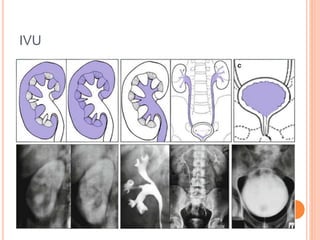

IVU

 Kidney film 3 min.

 A KUB radiograph is obtained to assess temporal

symmetry and opacification.

 Compression? (Contraindications ).

 Bladder film early

(suspected bladder

lesion).

 KUB after release of

compression( 15 min).

 delayed images for

bladder distention, and

oblique, prone, or post-

void images.

INTERPRETATION OF IVU

 Renal size.

 position of the kidney.

 Renal parenchyma at

nephrographic phase.

 Renal contour

(interpapillary line).